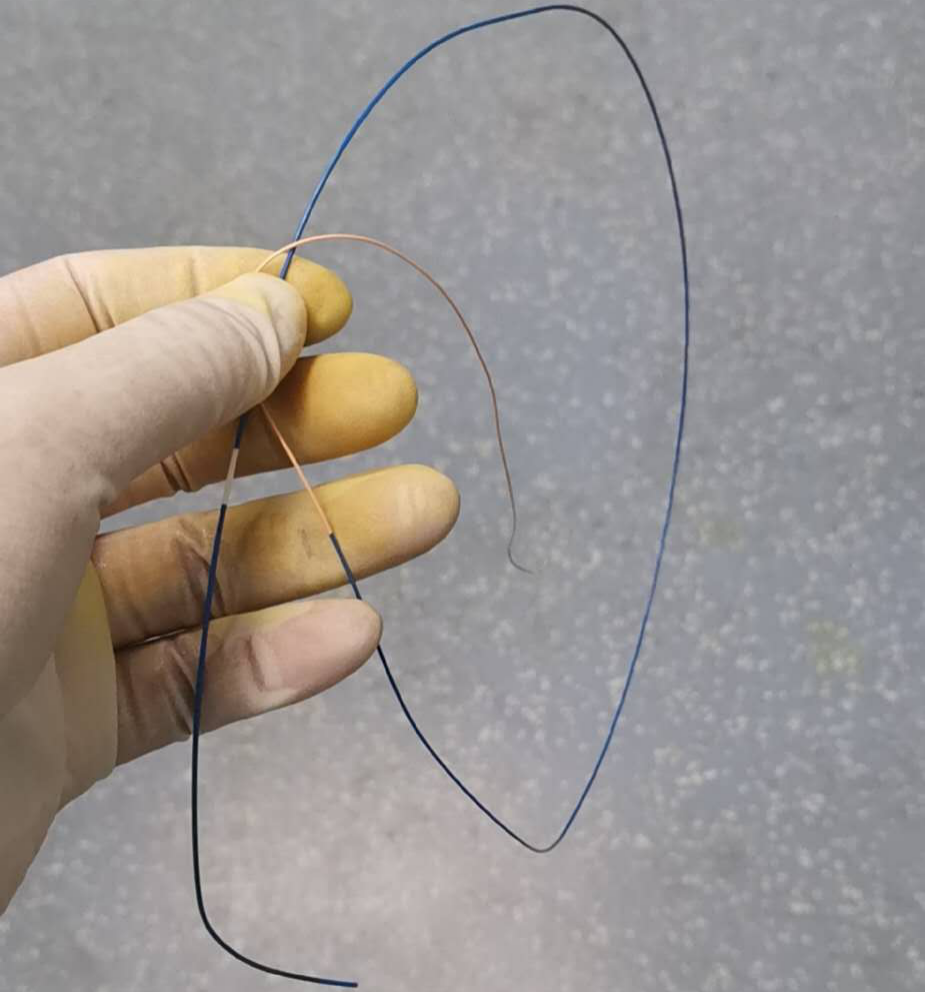

1. 通过椎动脉先将Echelon 10微导管在导丝导引下超选至远端动脉瘤,填塞弹簧圈(Cosmos 4mm/12cm,Jasper 3.5mm/10cm,Axium 3mm/8cm,Jasper 2.5mm/8cm),然后逐渐回撤微导管至近端动脉瘤填塞(Axium Prime 4mm/12cm),最后可见向畸形团供血明显减弱,远端动脉瘤不显影,近端动脉瘤仍有显影。

用Apollo微导管超选大脑中动脉M1段分支血管直至畸形团内,进行微导管造影确认微导管进入畸形团,DMSO冲管,缓慢注射Onyx 18,路图下可见胶在畸形团内弥散,最后颈内动脉造影可见畸形团完全不显影,但是胶反流导致拔管困难,透视下可见血管移位变形明显。

考虑到患者术前癫痫,且介入术中患者拔管困难,予以行开颅手术切除畸形血管团,并拔出微导管。术中可见微导管及注射的Onyx胶(血管内黄色部分及黑色部分),游离血管后近端用临时阻断夹阻断,远端剪断,打开临时阻断夹将微导管自股动脉鞘拔出,然后切除畸形团。术后复查头颅CT提示钙化及介入术中胶均已切除。